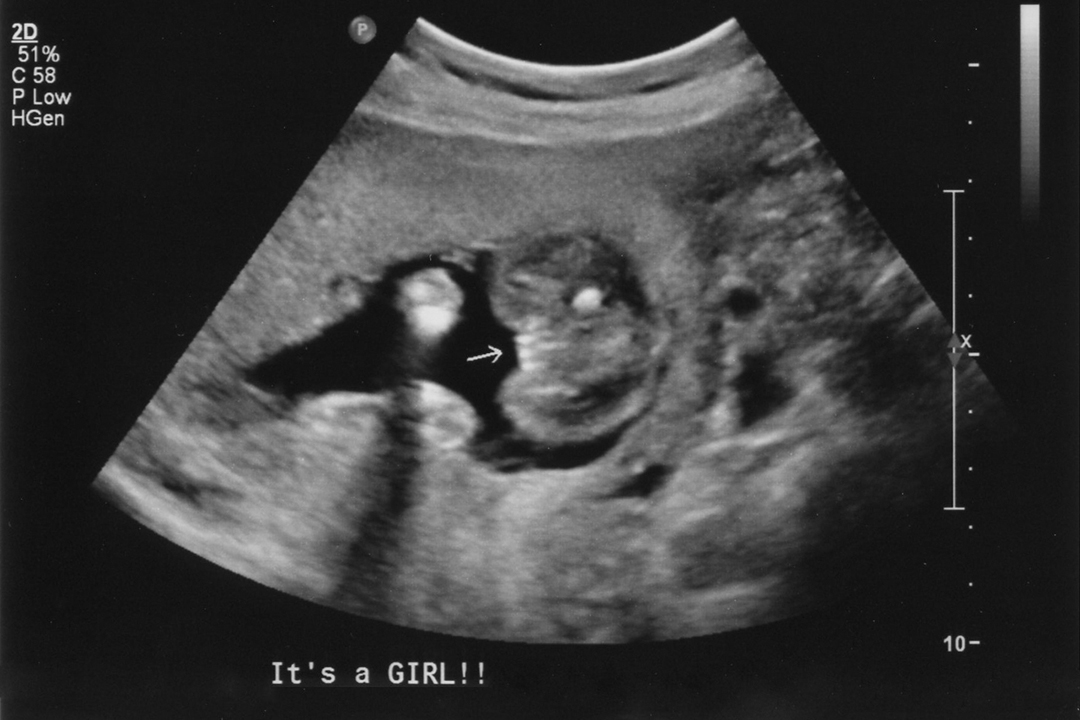

Baby Boy Potty Shot 13 Weeks . The bladder is more likely to be seen in a boys potty shot due to their low bladder position and their genitals being on top of their lower abdomen. I had a shot like that at 13 weeks, and our tech told us there was no gender in that shot. I’d honestly wait until you can get one at. I could see their penis clear as. I know it’s still really early and we may not even been able to tell. Your baby’s sex will not change but their genitalia is still developing and will certainly undergo changes in the next few weeks. Get the blood test or wait until your anatomy scan. People of the internet are no better at guessing your child’s sex than ultrasound. We just had it confirmed boy. She said she wasn't certain if it was a cord or penis. Unfortunately these aren't the potty shots you need at 13weeks. 13 week potty shot (from a few weeks ago). I was 13 weeks exact and she gave us a potty shot is this a boy or girl? Fwiw, i don’t have print outs but i did see potty shots of my boys at 12w and each time it was incredibly obvious that they were boys. Jul 8, 2020 at 2:11 pm.

The bladder images as a black circle under the penis and scrotum and to an untrained eye may look like the anus. I had a shot like that at 13 weeks, and our tech told us there was no gender in that shot. Unfortunately these aren't the potty shots you need at 13weeks. People of the internet are no better at guessing your child’s sex than ultrasound. I was 13 weeks exact and she gave us a potty shot is this a boy or girl? I know it’s still really early and we may not even been able to tell. 13 week potty shot (from a few weeks ago). Fwiw, i don’t have print outs but i did see potty shots of my boys at 12w and each time it was incredibly obvious that they were boys. Your baby’s sex will not change but their genitalia is still developing and will certainly undergo changes in the next few weeks. I’d honestly wait until you can get one at.

Baby Boy Potty Shot 13 Weeks We showed the pic to the nurse at our on office, and she said totally a boy. The bladder images as a black circle under the penis and scrotum and to an untrained eye may look like the anus. We showed the pic to the nurse at our on office, and she said totally a boy. I know it’s still really early and we may not even been able to tell. She did the blood doppler thingy and it was red/. She said she wasn't certain if it was a cord or penis. 13 week potty shot (from a few weeks ago). I could see their penis clear as. Get the blood test or wait until your anatomy scan. Fwiw, i don’t have print outs but i did see potty shots of my boys at 12w and each time it was incredibly obvious that they were boys. Penises and clitorises are close to the same size until around 14 weeks. Jul 8, 2020 at 2:11 pm. The bladder is more likely to be seen in a boys potty shot due to their low bladder position and their genitals being on top of their lower abdomen. People of the internet are no better at guessing your child’s sex than ultrasound. I’d honestly wait until you can get one at. Unfortunately these aren't the potty shots you need at 13weeks.